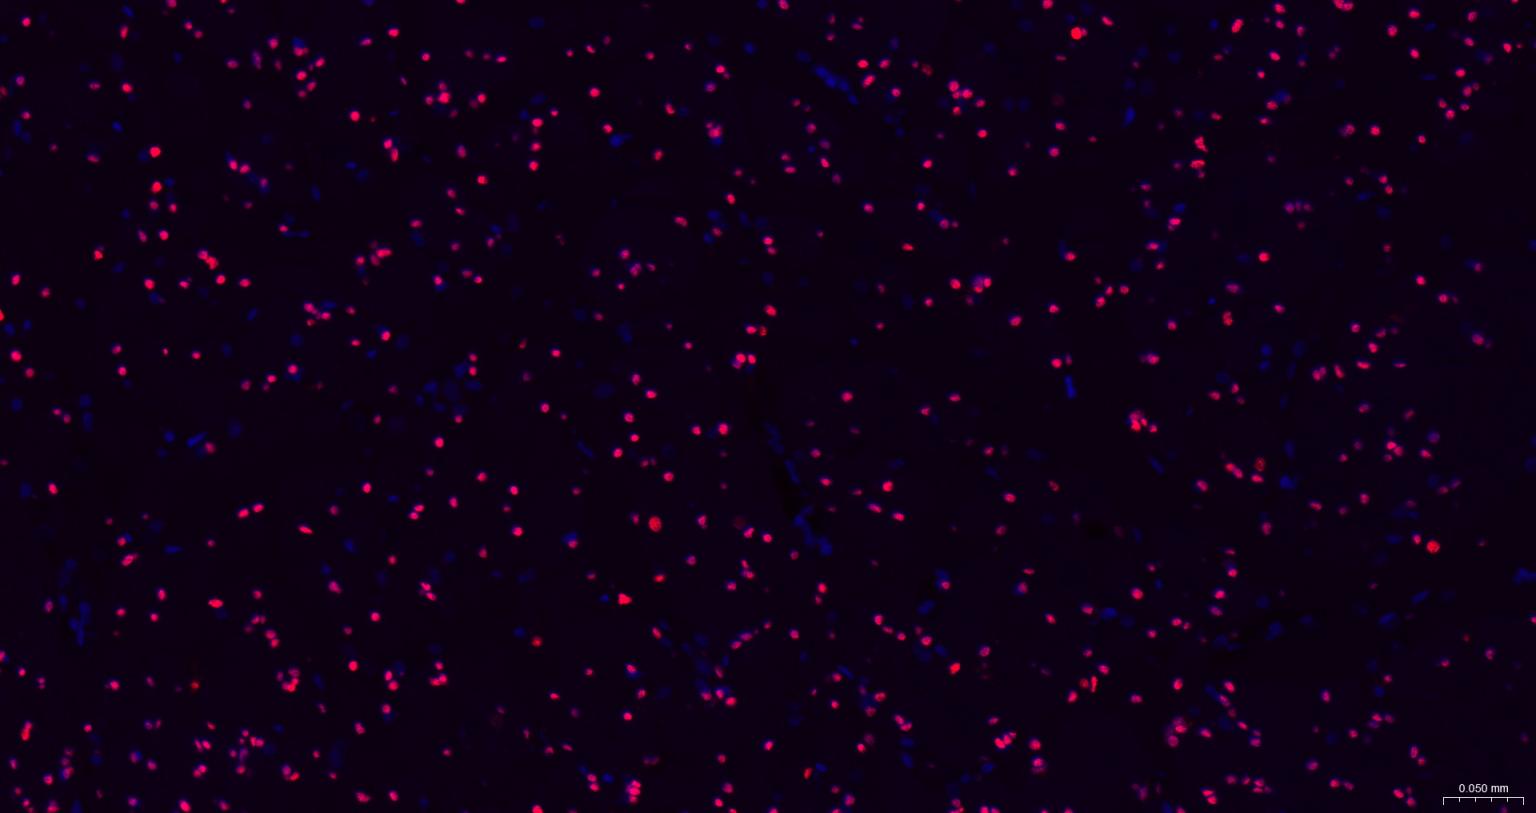

Paraformaldehyde-fixed, paraffin embedded Human Breast; Antigen retrieval by boiling in sodium citrate buffer (pH6.0) for 15 min; The section was incubated with SOX10 Monoclonal Antibody, Unconjugated (bsm-60234R) at 1:200 overnight at 4°C. Followed by conjugated Goat Anti-Rabbit IgG antibody (Red, bs-0295G-BF594), DAPI (blue, C02-04002) was used to stain the cell nuclei.